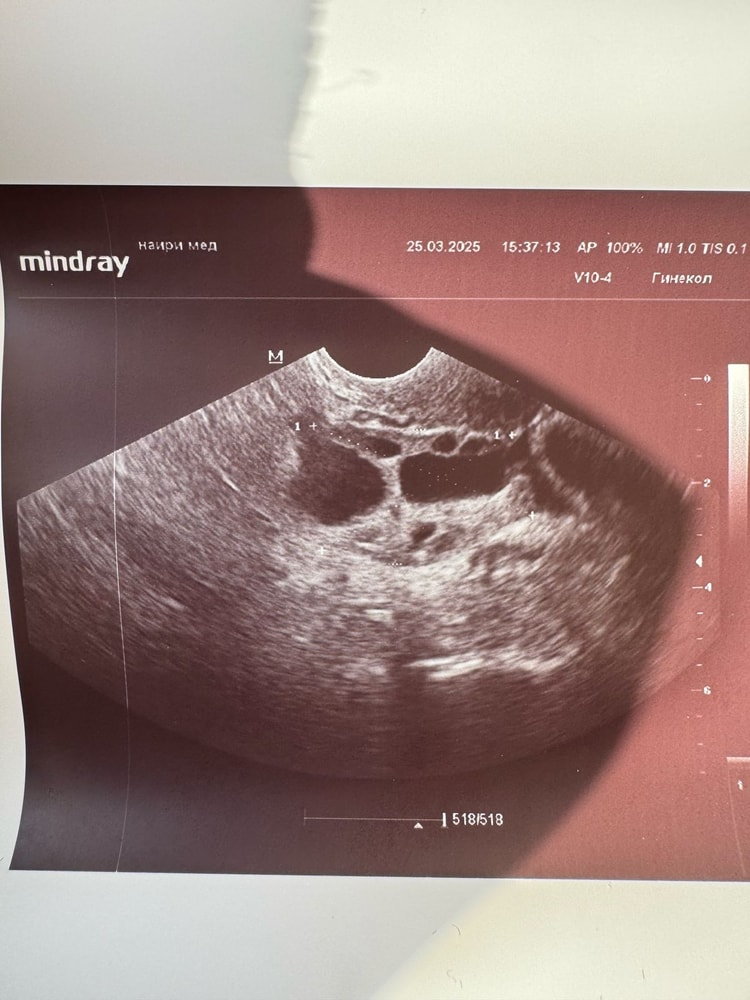

Алена, 22.02 - УЗИ фолликул 19 мм, на следующий день угол ХГЧ был 3000. Ой, тут главное сейчас успеть в срок!

Алена, ну слушай, я бы тоже поставила завтра. Будет около 20 точно уже Овуляция была на следующий день, 24 числа. Ощутимая очень

Горохова Диана, моя врач в отпуск ушла, к сожалению( а связи с ней напрямую нет. В прошлый раз мы ставили с ней укол овитрель на размере 19 мм. Но это было на стимуляции. Сейчас мне кажется, что еще маловат, а вот если завтра поставить вечером, он уже будет 19,8 + один день точно дозревать будет после укола.. около 21 мм будет.. Лишь бы яйцеклетка была хорошая, но тут уже не угадаешь 🫣 Просто боюсь ждать 2 дня, чтобы в кисту не перерос. Спасибо ❤️